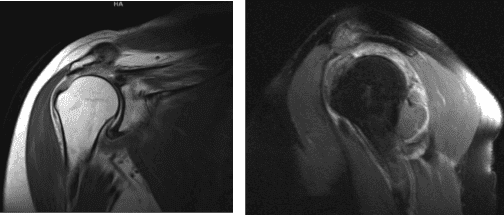

The patient presented an MRI result and showed complete tears of the supraspinatus and infraspinatus tendons with retraction as described. Subscapularis tendinosis with superimposed low-grade intrasubstance partial-thickness tear. Mild supraspinatus and infraspinatus muscle atrophy.

MRI right shoulder non-contrast